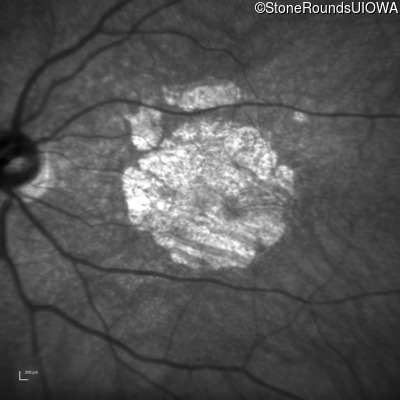

Blue Autofluorescence - Right - 10/300

Exemplar